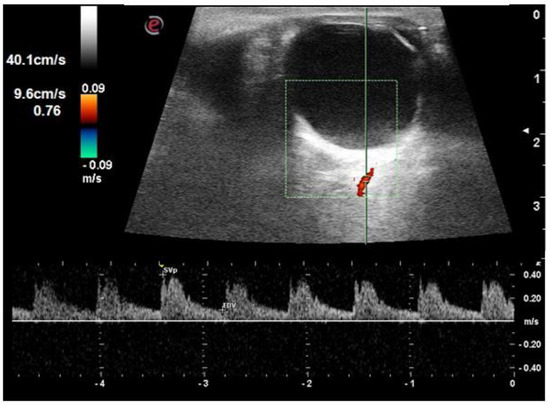

| PSV short posterior ciliary arteries (cm/s) | 19.1 ± 2.5 | 18.0 ± 4.2 | 16.7 ± 4.9 | 0.030 |

| EDV short posterior ciliary arteries (cm/s) | 5.9 ± 0.7 | 5.1 ± 1.3 | 4.3 ± 1.0 | <0.001 |

| RI short posterior ciliary arteries | 0.69 ± 0.03 | 0.71 ± 0.03 | 0.73 ± 0.5 | <0.001 |